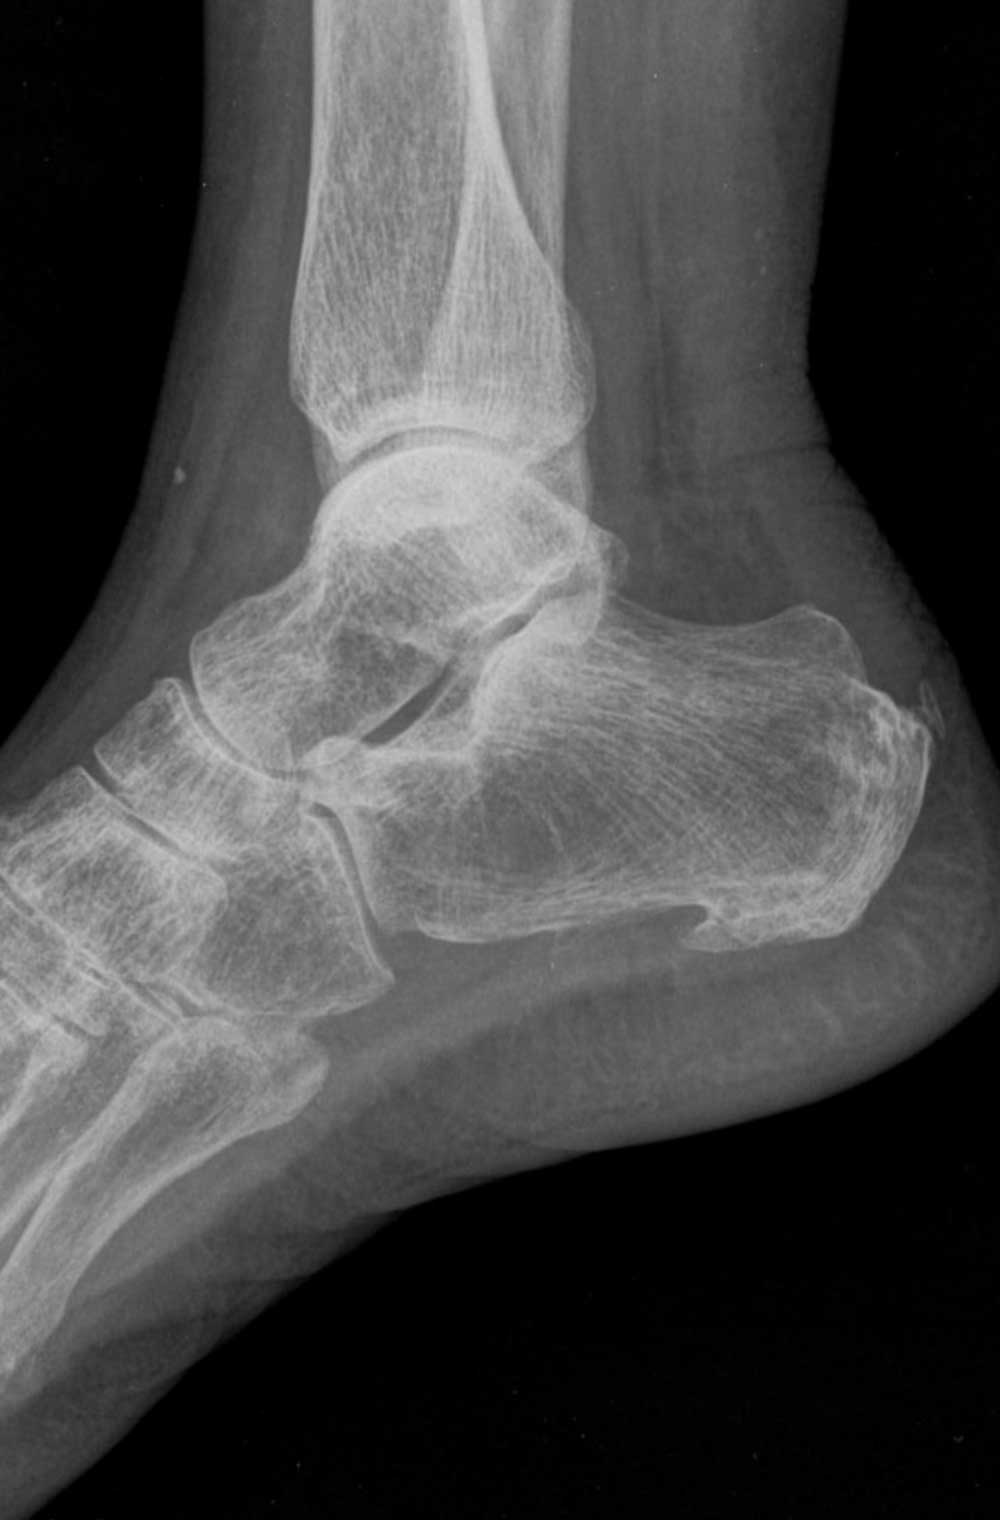

A sarkantyú, vagyis a sarokcsonton megjelenő csontkinövés sem minden esetben nevezhető bűnbaknak. Ugyan a röntgenfelvételeken gyakran látható, a kutatások szerint azonban nem áll egyértelmű összefüggésben a fájdalom mértékével.